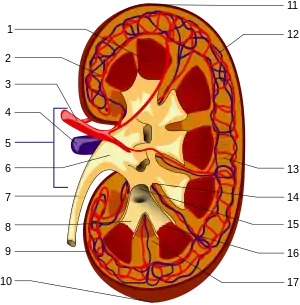

The functional substance, or parenchyma, of the kidney is divided into two major structures: the outer renal cortex and the inner renal medulla. Grossly, these structures take the shape of eight to 18 cone-shaped renal lobes, each containing renal cortex surrounding a portion of medulla called a renal pyramid.[14] Between the renal pyramids are projections of cortex called renal columns. Nephrons, the urine-producing functional structures of the kidney, span the cortex and medulla. The initial filtering portion of a nephron is the renal corpuscle, which is located in the cortex. This is followed by a renal tubule that passes from the cortex deep into the medullary pyramids. Part of the renal cortex, a medullary ray is a collection of renal tubules that drain into a single collecting duct.

The tip, or papilla, of each pyramid empties urine into a minor calyx; minor calyces empty into major calyces, and major calyces empty into the renal pelvis. This becomes the ureter. At the hilum, the ureter and renal vein exit the kidney and the renal artery enters. Hilar fat and lymphatic tissue with lymph nodes surround these structures. The hilar fat is contiguous with a fat-filled cavity called the renal sinus. The renal sinus collectively contains the renal pelvis and calyces and separates these structures from the renal medullary tissue.[15]